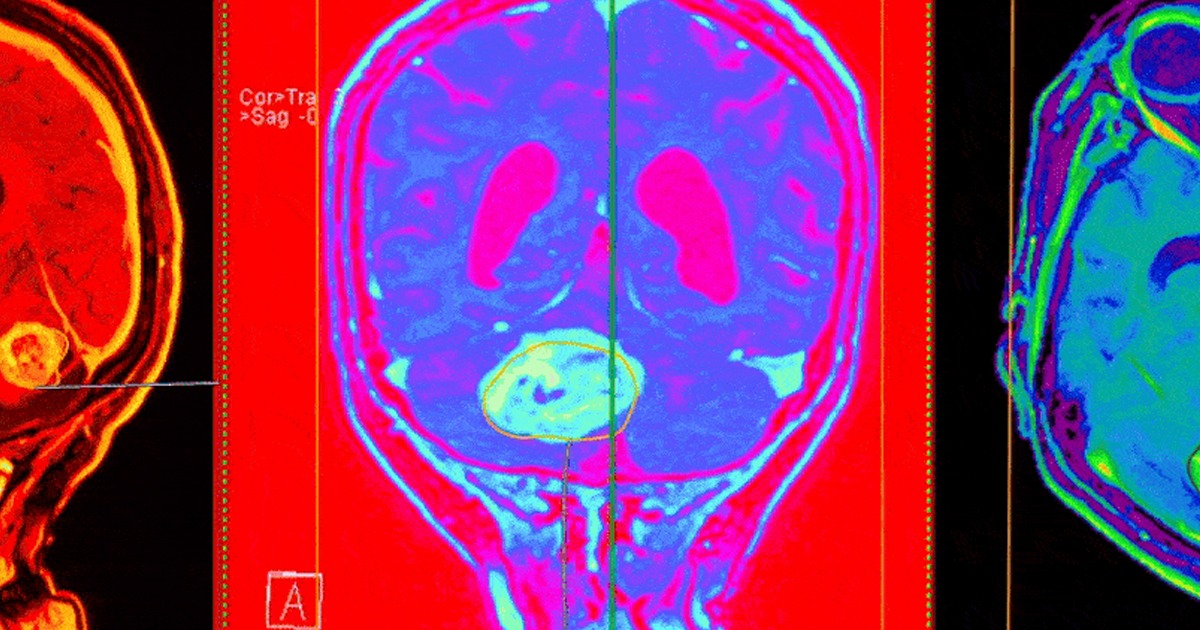

Nueva herramienta de IA mejora el diagnóstico de tumores cerebrales

Un sistema basado en modelos de deep learning distingue con alta precisión el glioblastoma de otros cánceres similares.

El diagnóstico preciso de tumores cerebrales es esencial para ofrecer a los pacientes un tratamiento adecuado y oportuno. Uno de los mayores retos en la neurooncología es diferenciar el glioblastoma, el cáncer cerebral más común y agresivo, de otros tumores que comparten características similares, como el linfoma primario del sistema nervioso central (PCNSL, en inglés). Una clasificación errónea puede tener consecuencias significativas, ya que ambos requieren estrategias terapéuticas muy distintas.